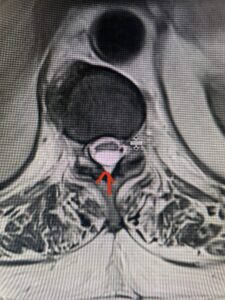

Fig: 2b Axial T2-weighted cervical MRI demonstrating spinal cord compression from C4-5 herniated disc (red arrow)

This 47-year-old male who four months prior was lifting weights developed sharp pain in his neck. After that he developed progressive numbness in his arms, neck pain and headache. He said that the right arm was worse than the left. On examination the patient had long tract weakness on the right side which included his triceps, finger extensors, hip flexors, and dorsiflexors. The patient did not have hyperreflexia. MRI (Fig. 2) demonstrated a massive, extruded disc herniation with severe cord compression. The patient because of progressive myelopathy and spinal cord compression was indicated for anterior cervical discectomy and fusion at C4-5 (Fig. 3). Patient had significant improvement of weakness and numbness post operatively.

Fig. 2a Sagittal T2-weighted cervical MRI demonstrating large C4-5 herniated disc with spinal cord compression (red arrow)